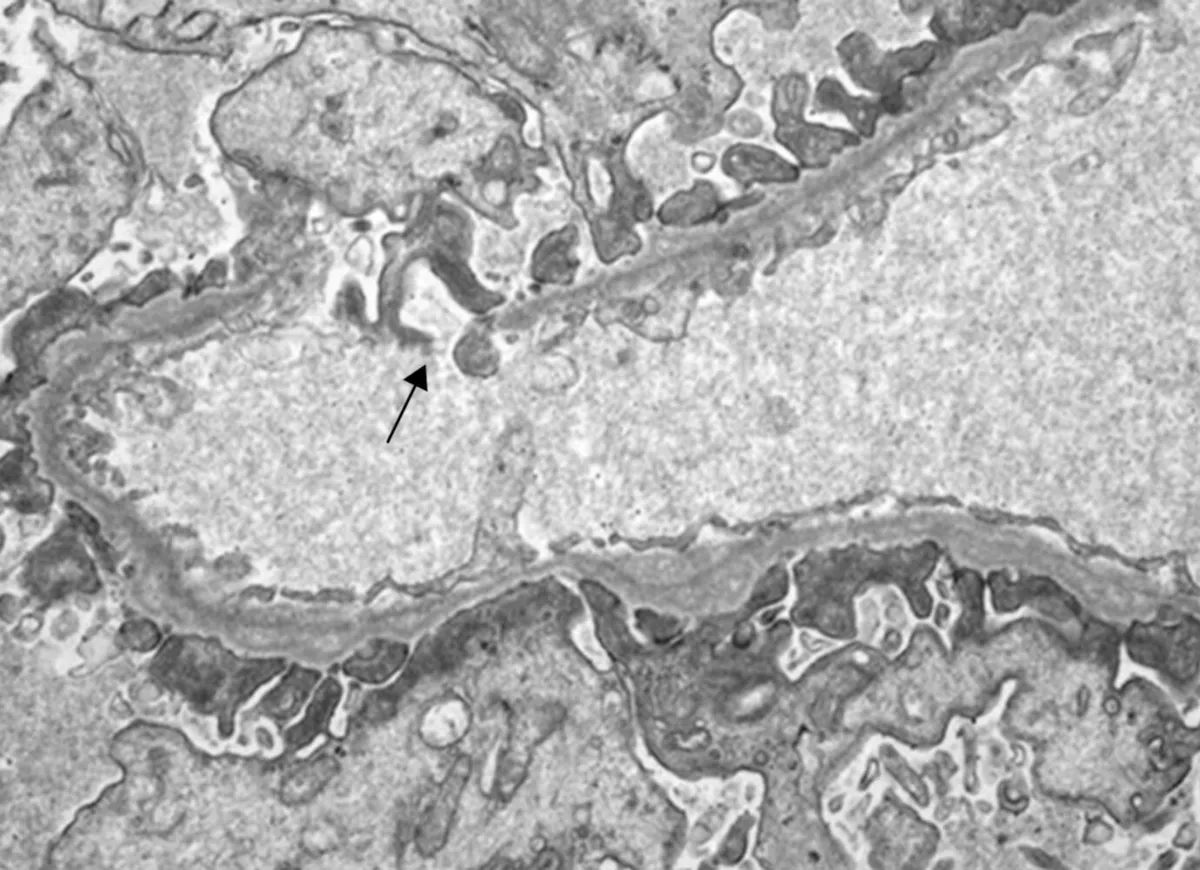

A DRPAD não é contraindicação à DP — e, na prática, muitos pacientes têm resultados comparáveis à hemodiálise. O “porém” está na mecânica: rins/hepatomegalia podem reduzir tolerância a volumes, aumentar risco de hérnias e extravasamentos, e piorar desconforto respiratório. Com técnica adequada (cateter presternal ou lateral, volumes menores, cicladora noturna e decúbito supino), a maioria das barreiras é contornável. Neste post, revisamos quando a DP é ótima, quando exigir cautela e como ajustar a prescrição para segurança e qualidade de vida.